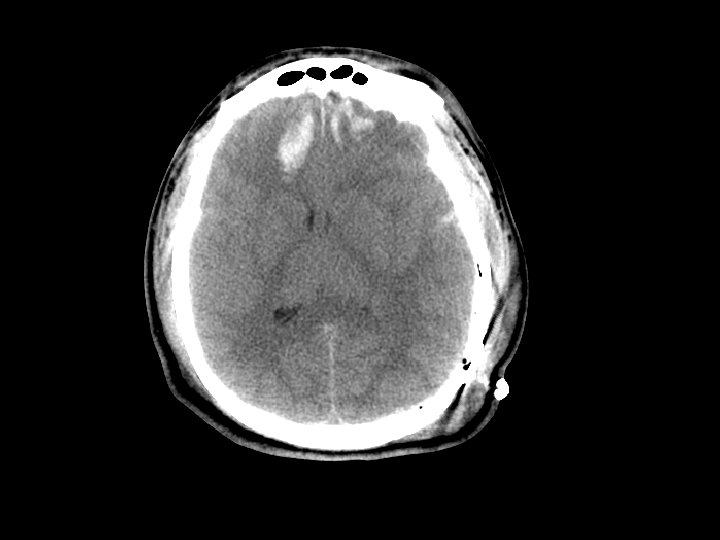

Máu tụ ngoài màng cứng (EDH) • Chảy máu ngoài màng cứng – Thường do động mạch (động mạch màng não giữa) nhưng cũng có thể do chảy máu tĩnh mạch • CT: hình tụ máu thấu kính lồi – Xuất huyết nằm khư trú do hạn chế trong khoảng giữa màng cứng và sọ • 5 -15% bệnh nhân CTSN có tụ máu ngoài màng cứng

Máu tụ ngoài màng cứng • Có nguy cơ tăng khối choán chỗ và gây thoát vị liềm não (giãn đồng tử) – “khoảng tỉnh và sau đó tử vong” • Quan sát được tụ máu ngoài màng cứng • Tụ máu ngoài màng cứng gây choán chỗ cần can thiệp phẫu thuật